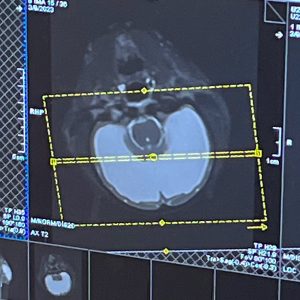

On March 9, 2023, Hogle Zoo’s animal care and health teams transported Juniper to the Utah MR Research Center at the University of Utah where an MRI of Juniper’s brain was conducted. The MRI showed a buildup of fluid around her brain, leading to the diagnosis of congenital hydrocephaly.

This diagnosis also helped us interpret that Juniper’s vision loss was due to fluid buildup, which created pressure on the optic area.